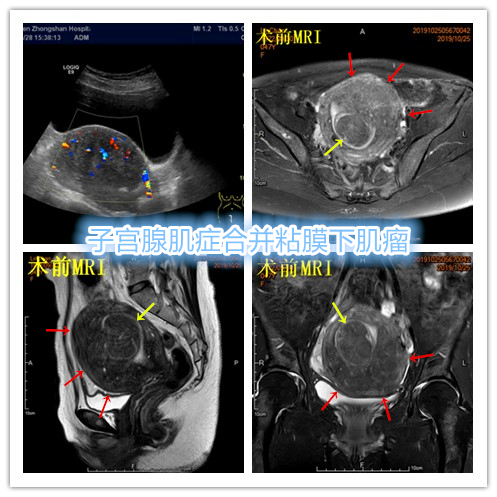

中年患者,发现“子宫腺肌症”10年余,近5年痛经、月经量增多等症状明显加重,导致贫血,严重影响生活质量。

- 术前彩超、磁共振检查显示子宫明显增大,子宫前壁可见弥漫型子宫腺肌症病灶,合并粘膜下、肌壁间子宫肌瘤。

横断位

冠状位

矢状位

- 术后患者痛经、月经量过多症状迅速缓解,生活质量明显改善。